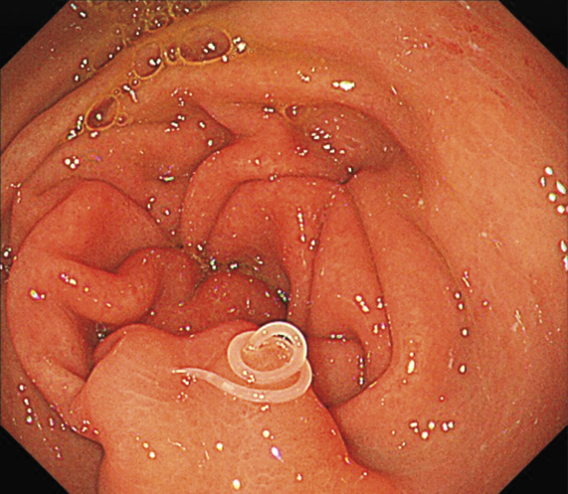

36歳の女性の胃の粘膜に寄生するアニサキス

内視鏡検査の結果、食道と胃の接続部や胃壁ばかりか、瞳孔の奥の眼底など上半身の粘膜という粘膜に寄生するたくさんのアニサキスの幼虫が確認された。

医療チームは内視鏡鉗子を使ってアニサキスの幼虫を除去し、その様子を写した動画を医学誌に発表した。